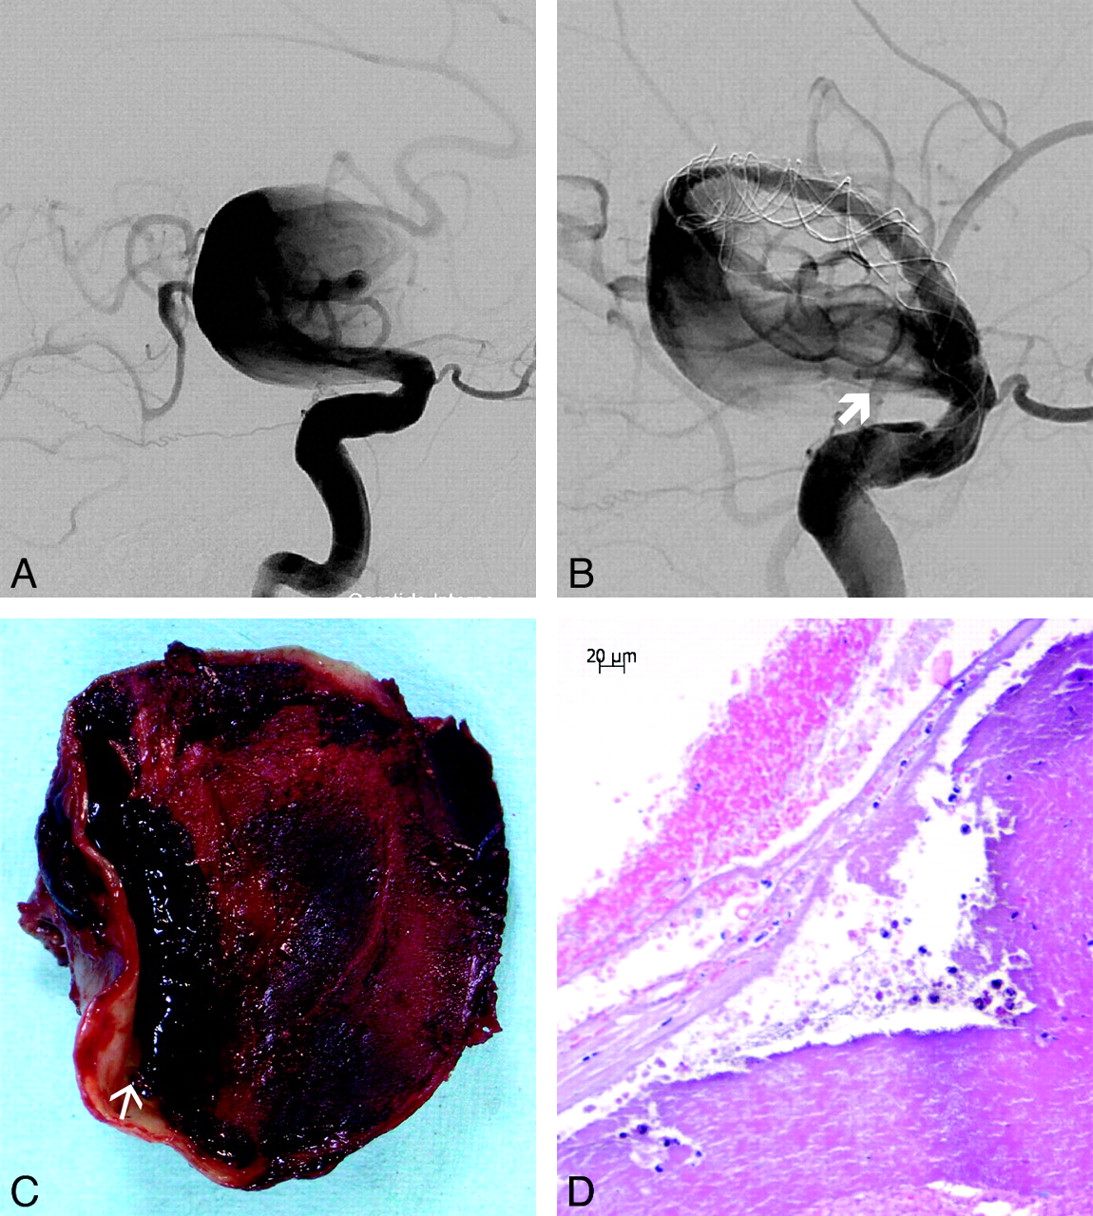

Pathology Results

Postmortem dissection and detailed histopathologic examination were performed in patients 5 and 6, showing a massive subarachnoid hemorrhage. Macroscopically, both aneurysms showed massive organizing intraluminal thrombus and mural thinning at the site of rupture (Fig 2). Microscopically, the aneurysm wall at the site of the rupture was extremely thin, with mural necrosis, loss of fibrous tissue and medial smooth muscle cells, and infiltration by macrophages extending from the adventitial surface (Fig 3).

Patient No. 5. A and B, Giant fusiform aneurysm of the right distal ICA, right oblique view before (A) and after FD implantation, with a persisting inflow jet (thick arrow) (B). C, Cross-section of the aneurysm after postmortem examination shows organized thrombus filling most the aneurysm lumen. Note a dissecting cavity with liquefied clot between the organized thrombus and the thick part of the aneurysm wall (arrow). D, Microscopic view of the aneurysm after HE-staining at the rupture site shows necrosis and almost complete disappearance of the aneurysm wall.